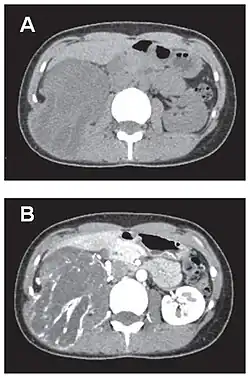

- Tumeur fibreuse solitaire du rétropéritoine

Aspect tomodensitométrique, sans (A) puis avec (B) injection de produit de contraste[44].

En tomodensitométrie[20],[31], quelle que soit la localisation, une tumeur fibreuse solitaire apparaît comme une masse tissulaire ovoïde ou lobulée, bien délimitée, refoulant les structures voisines sans les envahir. Elle se rehausse fortement après injection de produit de contraste. Les tumeurs de petite taille sont homogènes, mais les plus volumineuses présentent des plages hétérogènes de nécrose et d'hémorragie intra-tumorale. Il n'y a pas habituellement de calcifications et, lorsqu'elles sont présentes, elles sont de petite taille[31]. Les tumeurs malignes peuvent se présenter accompagnées de nodules pulmonaires métastatiques, et tendent à être plus volumineuses et plus hétérogènes[42].